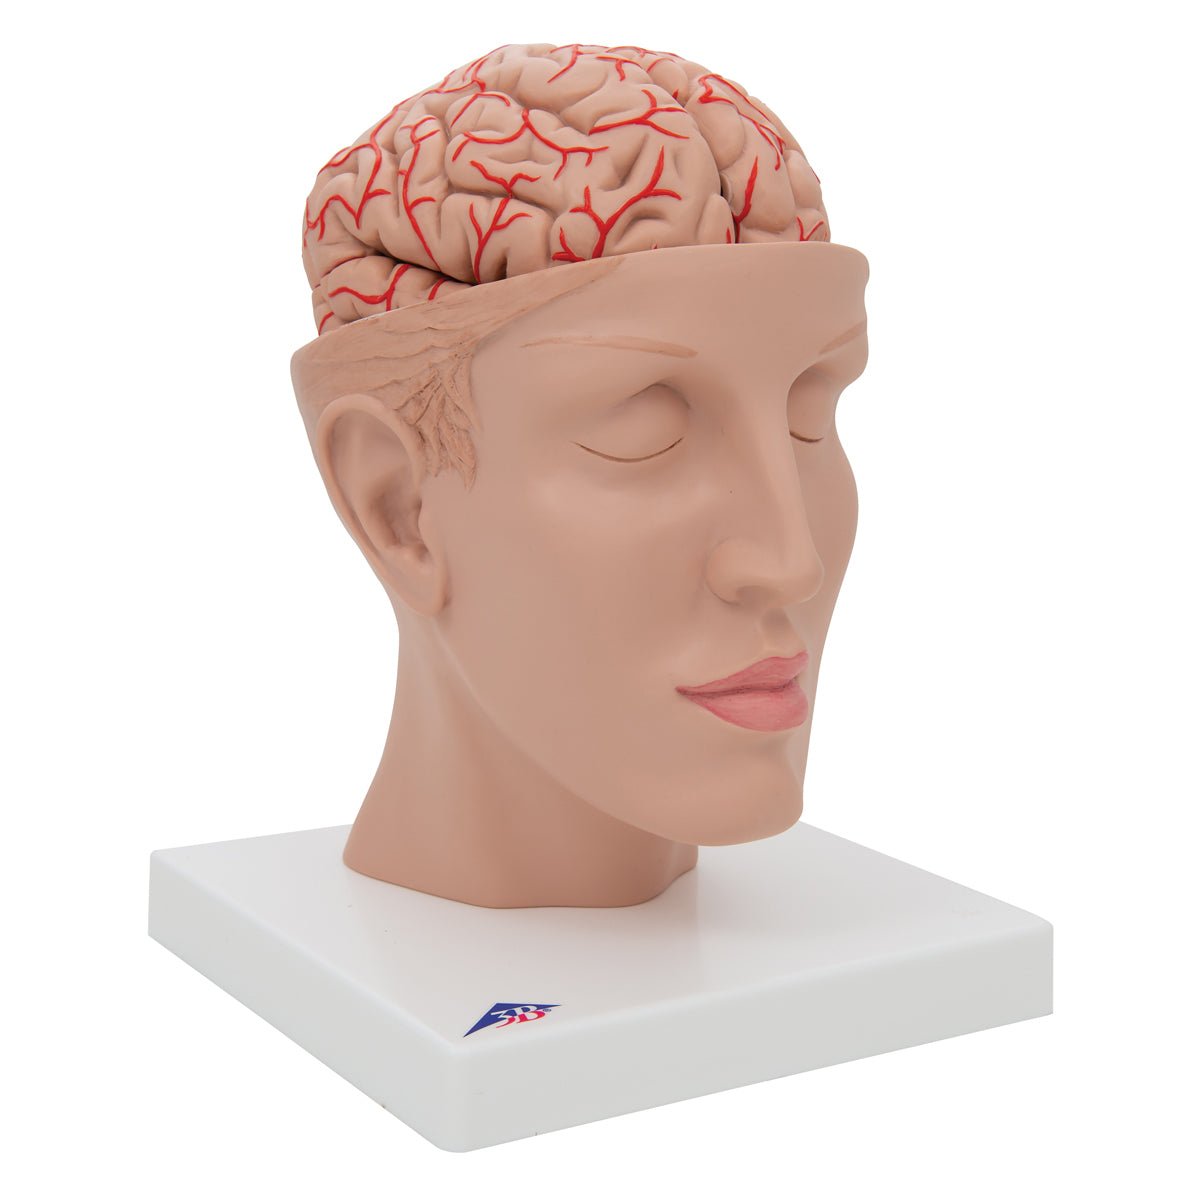

Selling anatomical models is the mainstay of eAnatomi, although we also spend a lot of resources developing our own anatomical materials such as posters. Anatomical models are used for various purposes and can show both defined tissues, organs and organ systems. Are you looking for a simple model of bone tissue or perhaps an advanced torso model based on MRI technology, you can find it all at eanatomi.com.